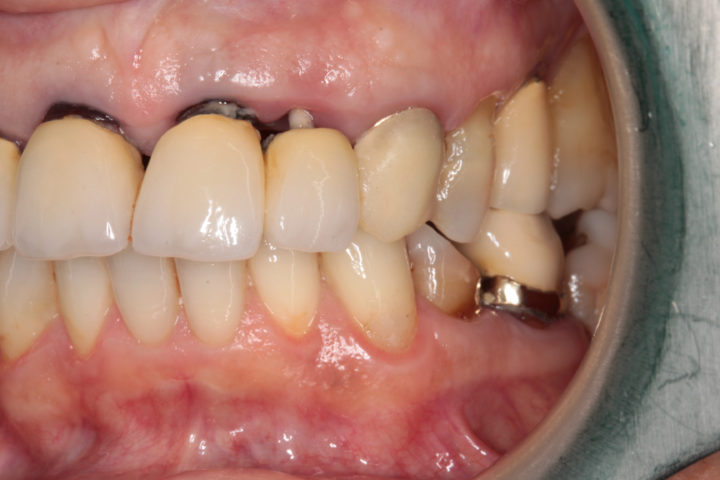

Situazione iniziale:

Incisivo superiore gravemente fratturato e non recuperabile. La frattura coinvolge la radice del dente, rendendo necessaria l’estrazione e la sostituzione con un impianto dentale.